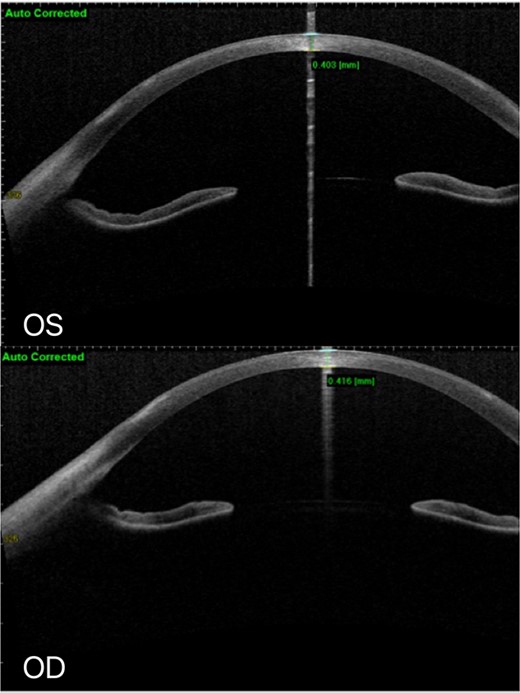

At the latest review, AS-OCT: No defect of corneal epithelium in both eyes, and white infiltration of superficial corneal stroma remained.